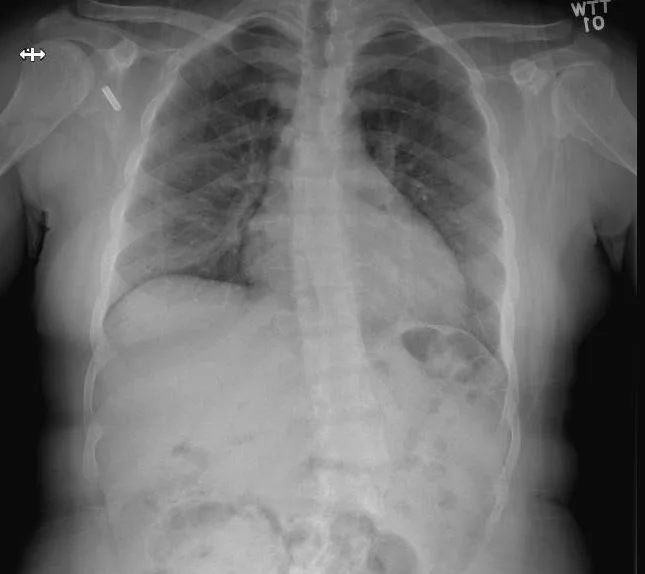

A 22 y.o. woman presents to the ED with low back pain after a fall in the bathtub. Her cxr and bone scan are shown.

Our patient had rickets with the classic “tie” sign ; increased uptake over the sternum on bone scan.

Our patient had scoliosis and multiple microfractures on bone scan.  On her current ED visit plain films showed no new fracture in the back and she was given symptomatic treatment.

Imaging in  all types of rickets shows pseudofractures which light up on bone scan where there is a stress fracture caused by insufficient mineralization.  They tend to occur  bilaterally in the mandible, at costochondral junctions ( causing the rachitic rosary)  andin the epiphyses of the knees.